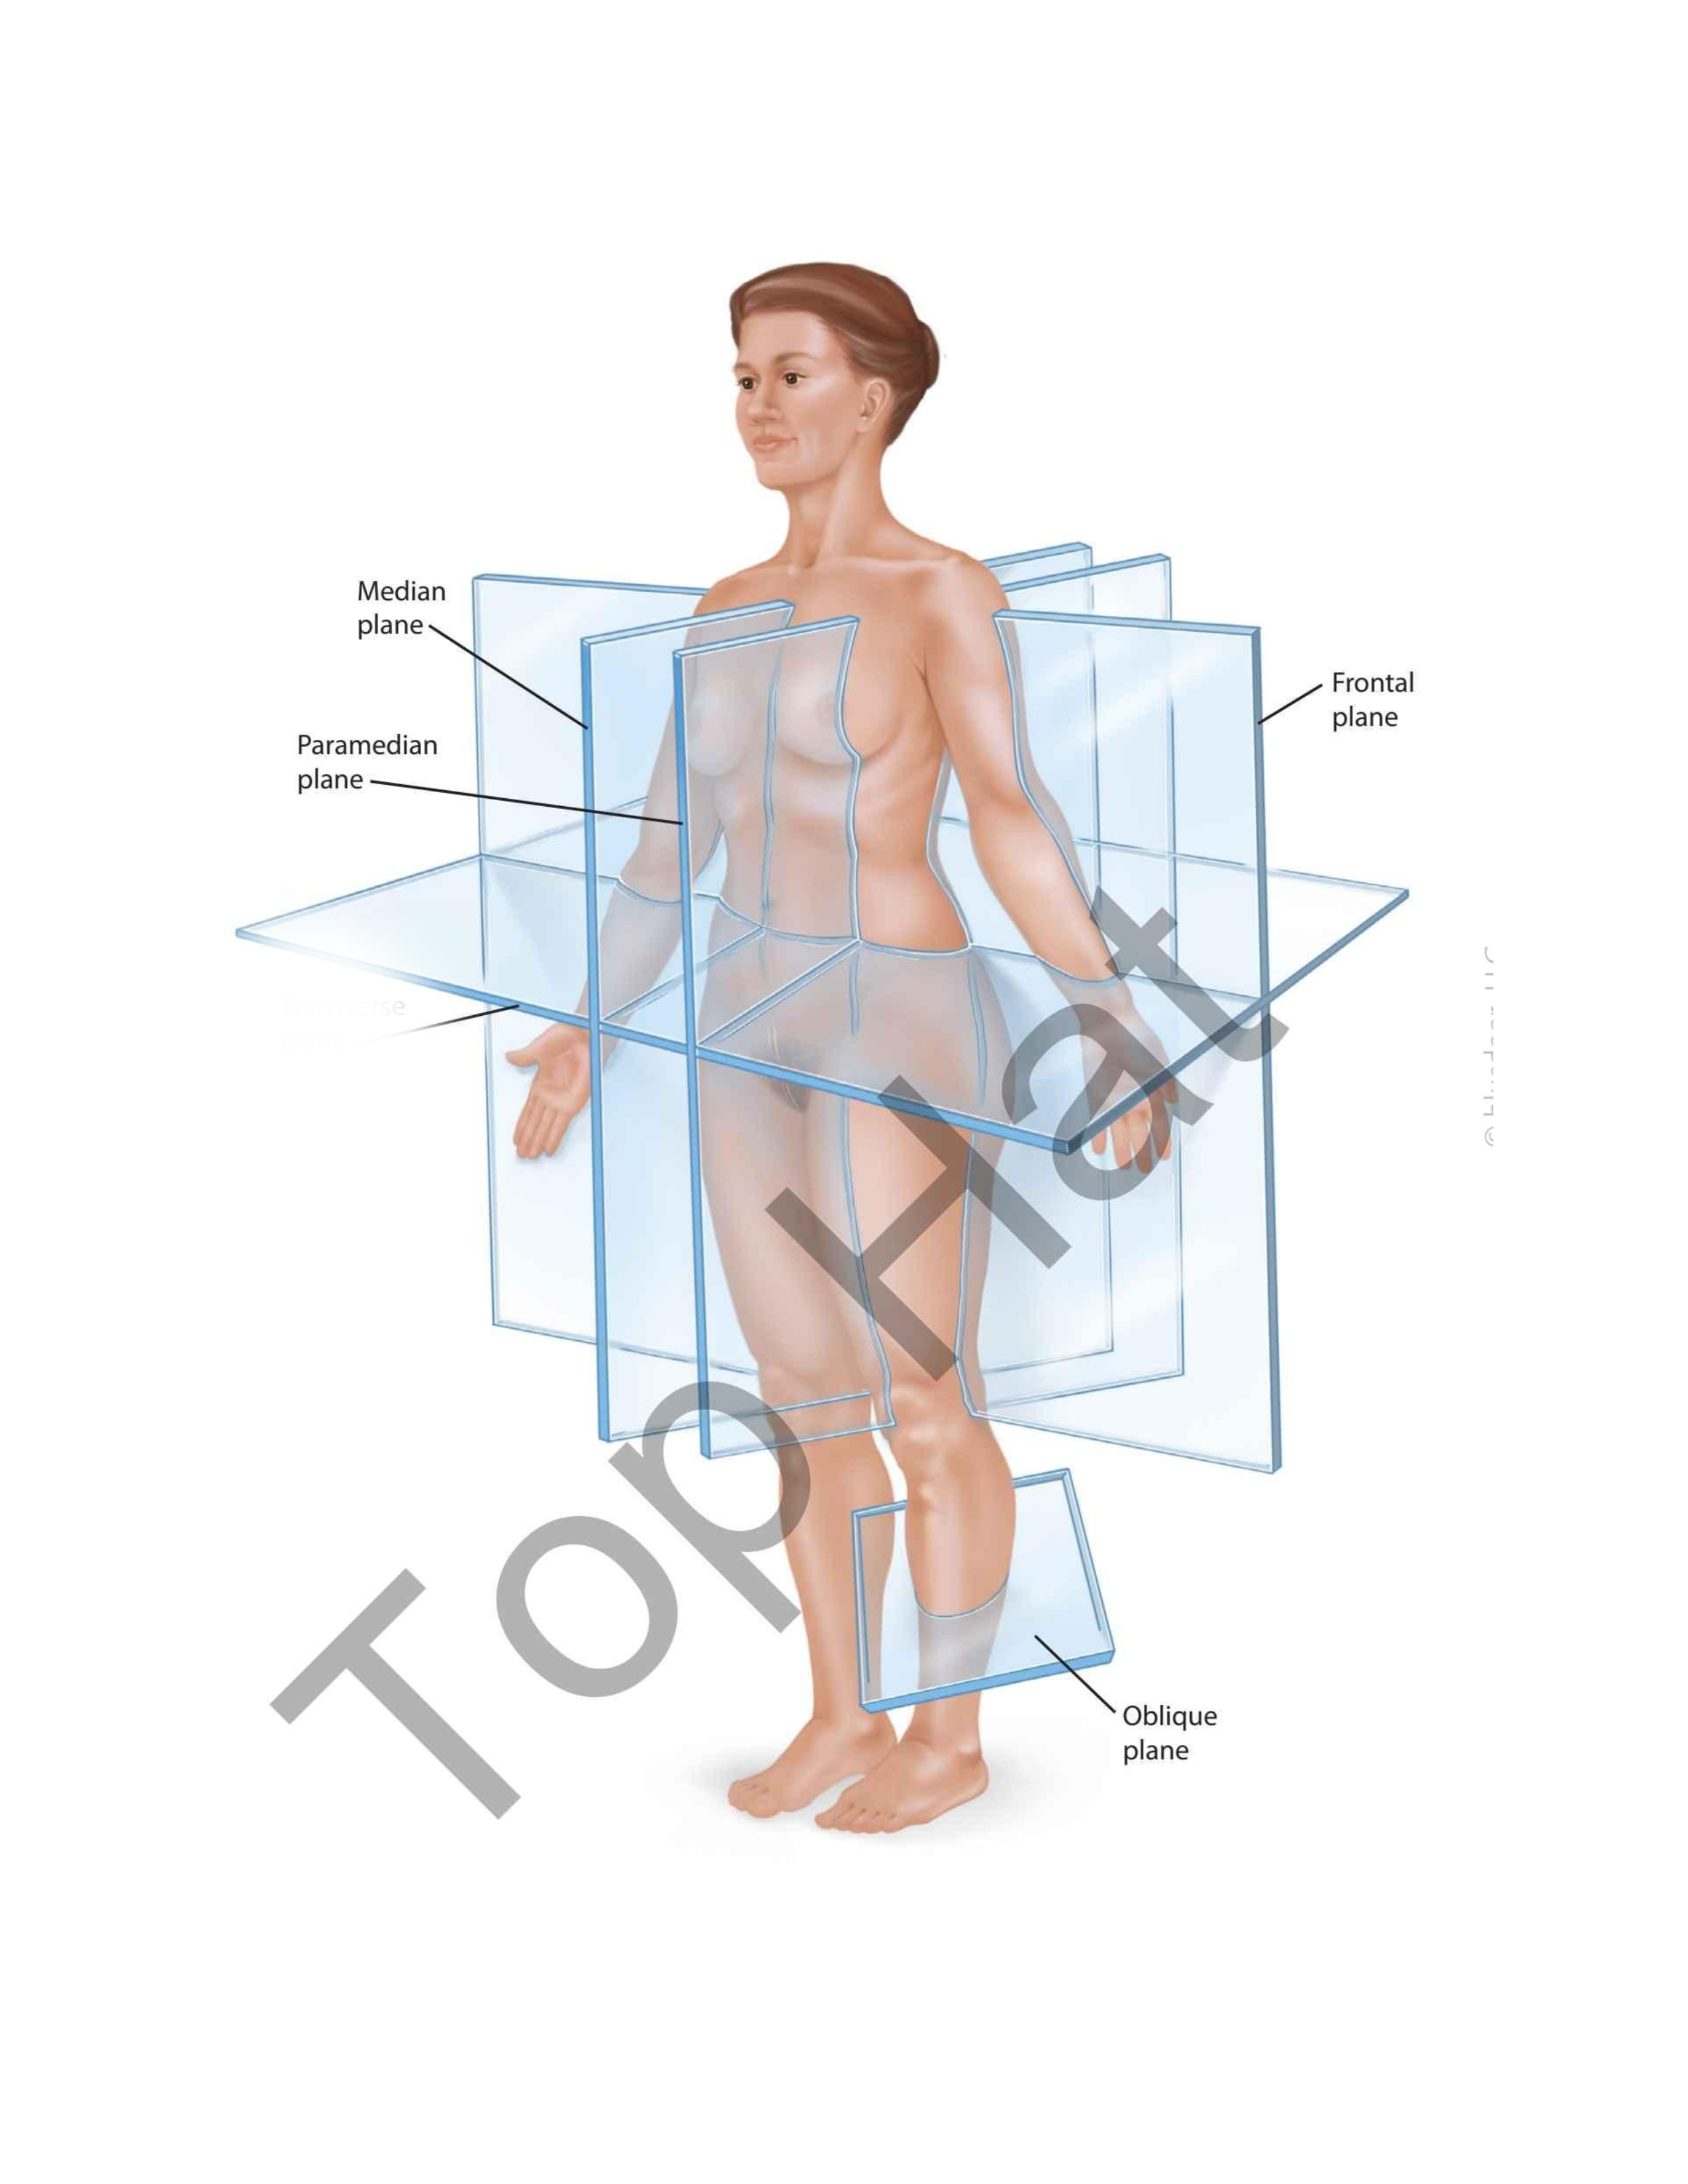

Median Plane

Frontal Plane

Oblique Plane

Transverse Plane

Paramedian Plane